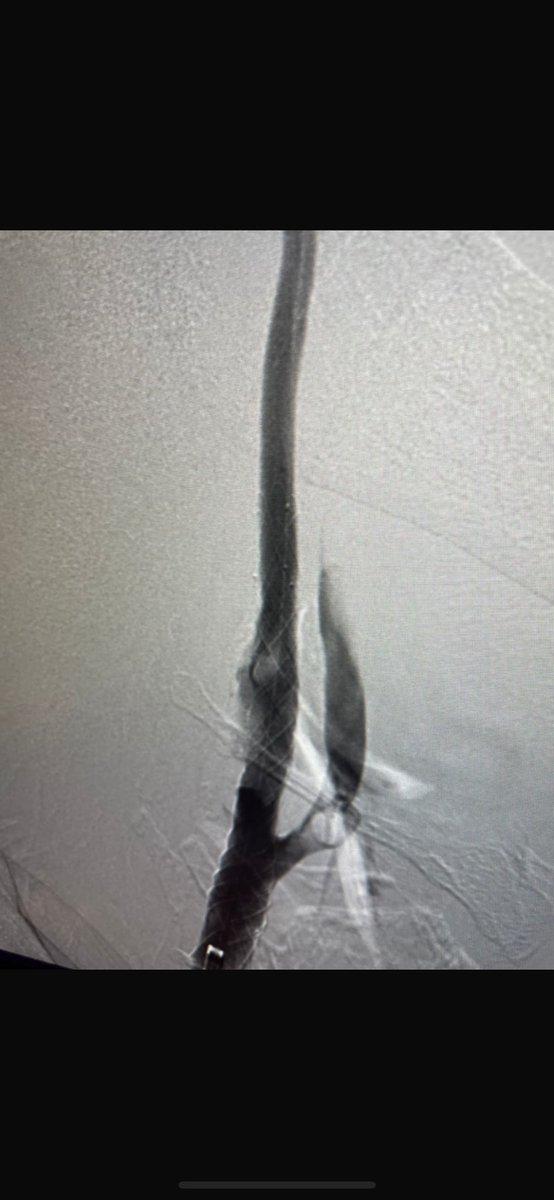

Successful carotid artery stenting in near total occlusion symptomatic stenosis case. 🧠 Timely intervention is key to stroke prevention. #Neurointervention #StrokePrevention #CarotidStenting #Endovascular

Successful carotid artery stenting in near total occlusion symptomatic stenosis case.

🧠 Timely intervention is key to stroke prevention.

#Neurointervention #StrokePrevention #CarotidStenting #Endovascular